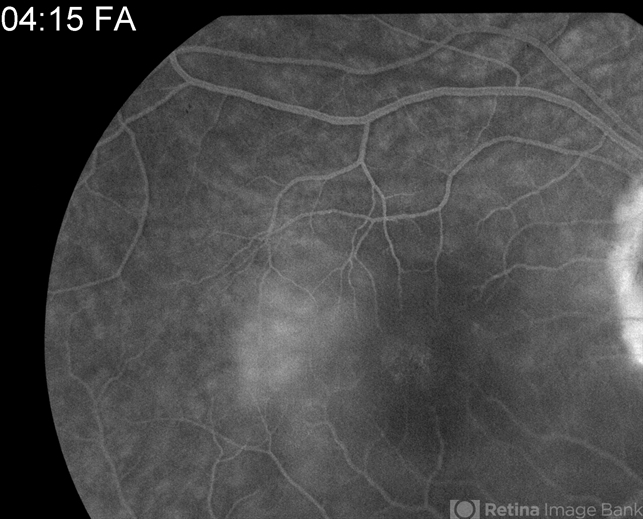

- Optic Nerve Pit Related Serous Detachment Treated by Vitrectomy with Laser and Gas

- congenital optic nerve pit, serous retinal detachment, pre-op, vitrectomy, vitreomacular surgery

- Pre-op late phase angiogram showing optic nerve pit and prior laser treatment at temporal aspect of optic nerve